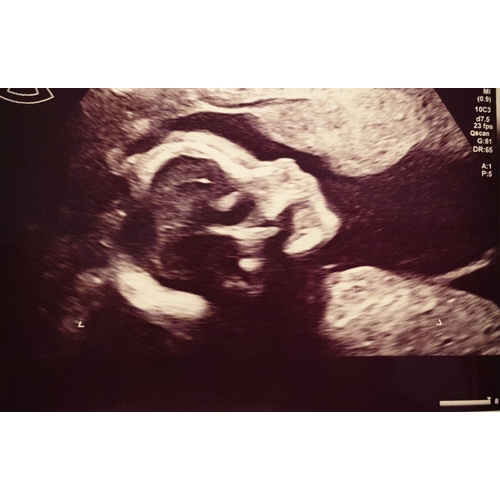

Ik neig meer naar girl. Een hele mooie baby in ieder geval dat zie ik zo al

Hahaha ja sorry ik weet al een tijdje dat de baby een meisje is. Was gewoon nieuwsgierig of iemand anders het ook zou zien aan de hand van een echo.

Ik heb namelijk de hele tijd het idee gehad dat het een jongetje zou zijn. Dus ik was enigzins toch verbaasd.

Ik ben super benieuwd hoe ze eruit gaat zien 🥰

Mooie neusje wat beetje rond loopt bij het puntje van de neus en hele mooie wat vollere lippen. Heeft 1 van jullie een andere afkomst of zit dat in de familie?